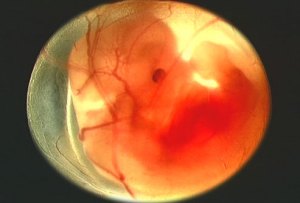

Fetus at 4 Weeks

All pictures came from:  http://www.webmd.com/baby/slideshow-fetal-development